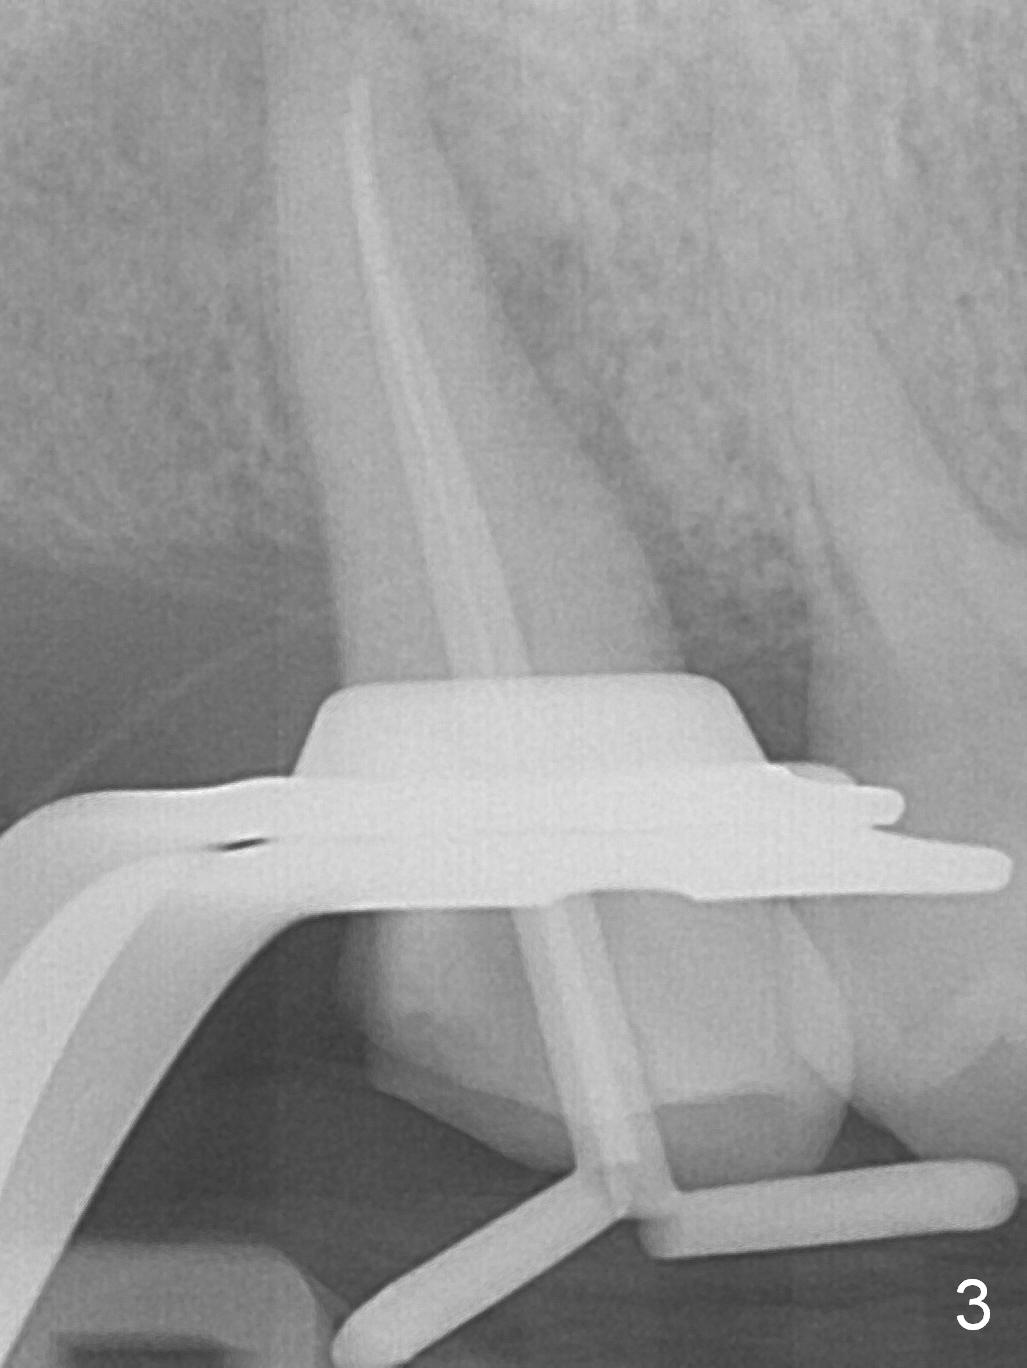

A 52-year-old woman presents to clinic with chief complaint "I can not bite in the upper right". Exam shows DO caries of the tooth #2 (Fig.1). After scaling & root planing and the tooth #1 extraction, pulpotomy is performed at #2. Two months later, pain recurs with swelling. When root canal therapy is finished at #2 (Fig.2-6), the tooth is found to have moderate mobility with guarded to poor prognosis. If the infection does not resolve, extraction and immediate implant seem to be necessary. Considering low bone density around the site of #2, a long implant is indicated (18 mm bone-level, Fig.7,8).